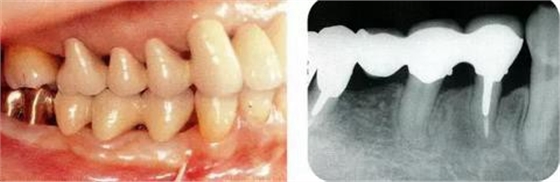

圖17-4(左),5 (右)▲術(shù)后9年的口腔內(nèi)照片和X線片,牙槽嵴平坦化,牙周探診數(shù)值很小。

圖18-1(左),2 (右)▲初診時口腔內(nèi)照片和X線片,右下4近中有較深的1壁性骨缺損,右下45有根接近。如果在這個情況下進(jìn)行骨外科處理,需要犧牲較多的右下3遠(yuǎn)中的牙槽骨。也會造成周圍骨形成較大的臺階。

圖18-7(左),8(右)▲佩戴最終修復(fù)體的口腔內(nèi)照片和X線片,牙槽骨平坦化,牙周袋探診2mm以內(nèi)。